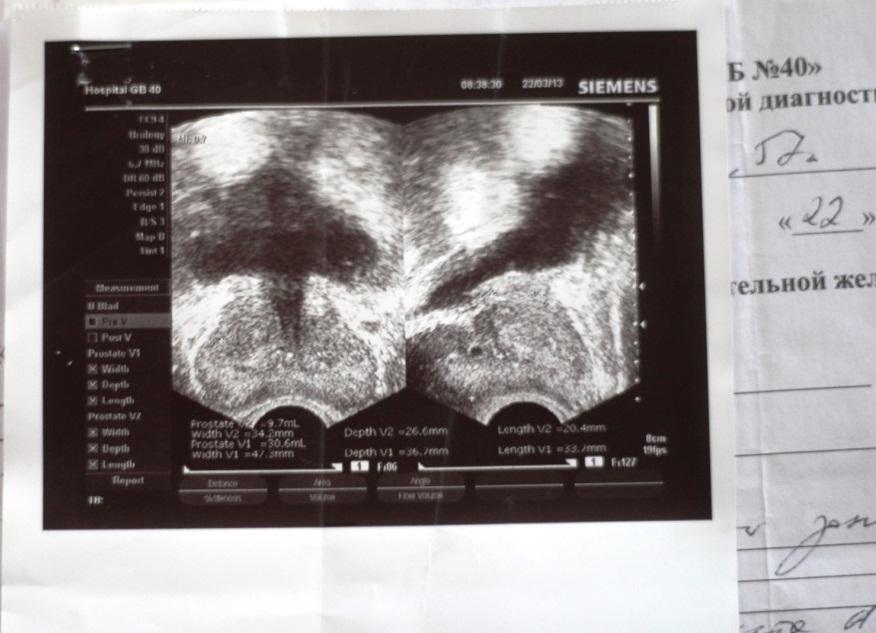

26.04.2013 г. меня направили к урологу с подозрением на аденому простаты, при обследовании выявили рост PSA до 28,76 нг/мл. Было проведено ТРПБ мультифокальная(?), поставлен диагноз аденокарцинома простаты, глисон 4+3б